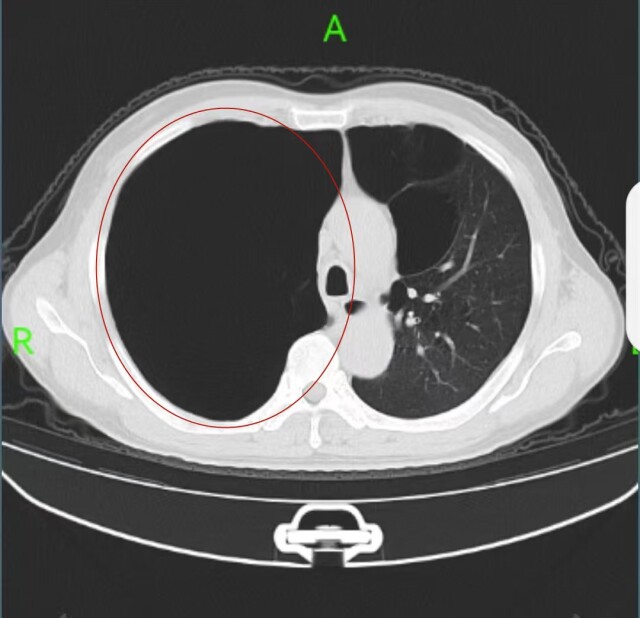

一般而言,无症状肺大疱无需治疗,但刘先生体内这个可不一般。“当时他自述感觉胸痛厉害、呼吸困难,我们检查后,着实吓了一跳,太大了!”该院胸外二病区主任周亚夫介绍,刘先生双肺长了多个肺大疱,特别是右肺内的肺大疱足有20×19×13cm大小,像一个气球一样,占据了右肺90%以上的空间,整个右肺如同消失不见,必须马上手术。

2月7日,刘先生接受了手术治疗。手术很顺利,“大气球”被成功摘除;效果很显著,术后第二天,其右肺已经恢复了70%。